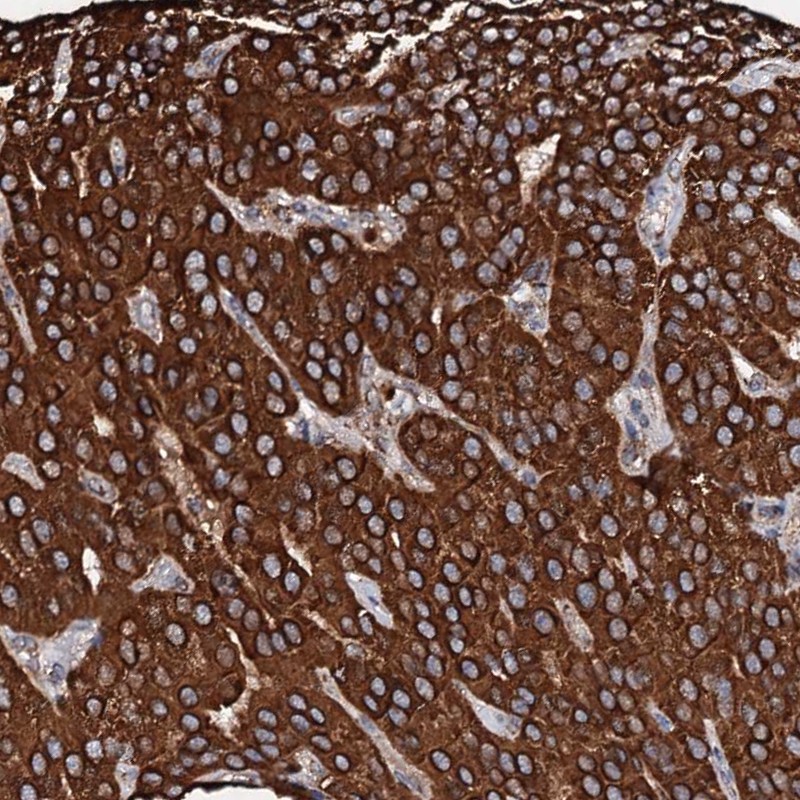

Immunohistochemical staining of human parathyroid gland shows cytoplasmic positivity in glandular cells.